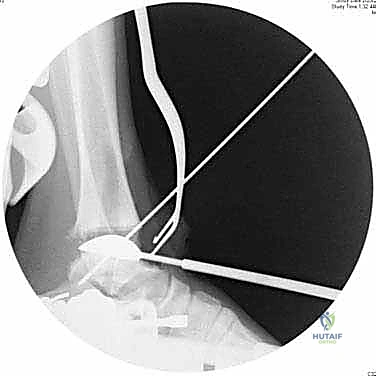

3. تحضير العظام باستخدام أدوات التوجيه

هنا تبرز روعة نظام INBONE™. يتم استخدام أدوات توجيه خاصة (Jigs) لضمان المحاذاة المثالية. يقوم الجراح بإزالة الأجزاء التالفة من غضروف وعظم الظنبوب (Tibia) والقعب (Talus) بدقة متناهية بالملليمتر.

4. إعداد القناة النخاعية وتركيب الساق (Stem)

يتم عمل ثقب دقيق في القناة النخاعية لعظمة الساق. يتم إدخال القطع المعيارية (Modular Stem Pieces) واحدة تلو الأخرى حتى يتم تحقيق التثبيت العميق والمستقر داخل العظم. هذا هو سر قوة نظام INBONE.

6. التحقق والإغلاق

يتم فحص المدى الحركي للكاحل الجديد وثباته تحت جهاز الأشعة السينية (Fluoroscopy) داخل غرفة العمليات للتأكد من المحاذاة المثالية بنسبة 100%. بعد ذلك، يتم إغلاق الشق الجراحي بغرز تجميلية، ووضع جبيرة ناعمة أو حذاء طبي واقٍ.